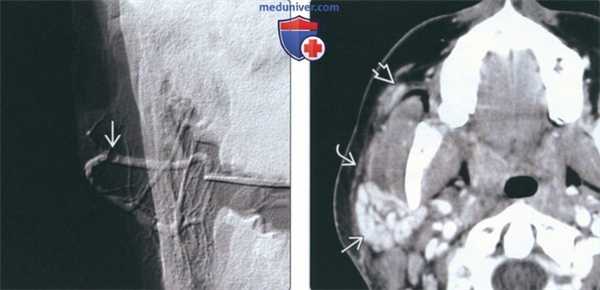

(Слева) На традиционной сиалограмме у пациента с паротидным сиаладенитом определяется легкое расширение протоков (реверсивная архитектура). Терминальные протоки и ацинусы практически не визуализируются. В дистальных отделах протока Стенсена определяется рентгенонегативный сиалолит.

(Справа) На корональной КТ с КУ(реконструкция) у семилетнего ребенка с острым вирусным паротитом определяется избыточное контрастное усиление увеличенной правой околоушной железы. Левая железа не изменена. Абсцессы, лимфаденопатия, конкременты отсутствуют.

(Слева) На обработанной традиционной сиалограмме визуализируется минимально обызвествленный сиалолит(муцинозная бляшка) в протоке Стенсена, выглядящая как дефект наполнения. Участки расширения протока перемежаются со стриктурами, что свидетельствует о сиалодохите.

(Справа) На КТ с КУ в аксиальной плоскости определяются типичные признаки острого паротита в виде интенсивного накопления контраста в сочетании с сиалолитом (протоковым конкрементом) в в дистальном сегменте протока Стенсена. Определяется также уплотнение вышележащей платизмы и подкожного жира, соотносящееся с острым воспалительным процессом.